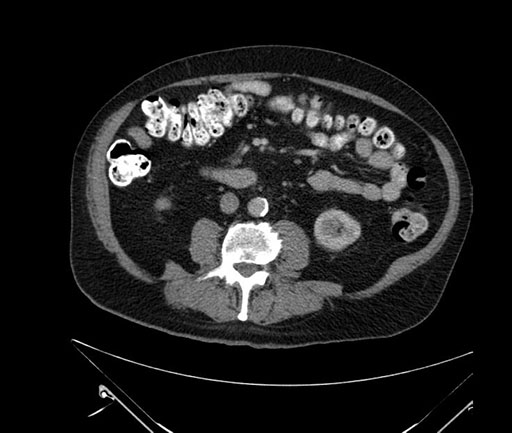

Imaging Analysis

Look through the patient's CT scan to identify any areas of concern for the necessary procedure.

Based on your CT findings, which issue(s) would give reason for "planned slowing down moment(s)" in this case?